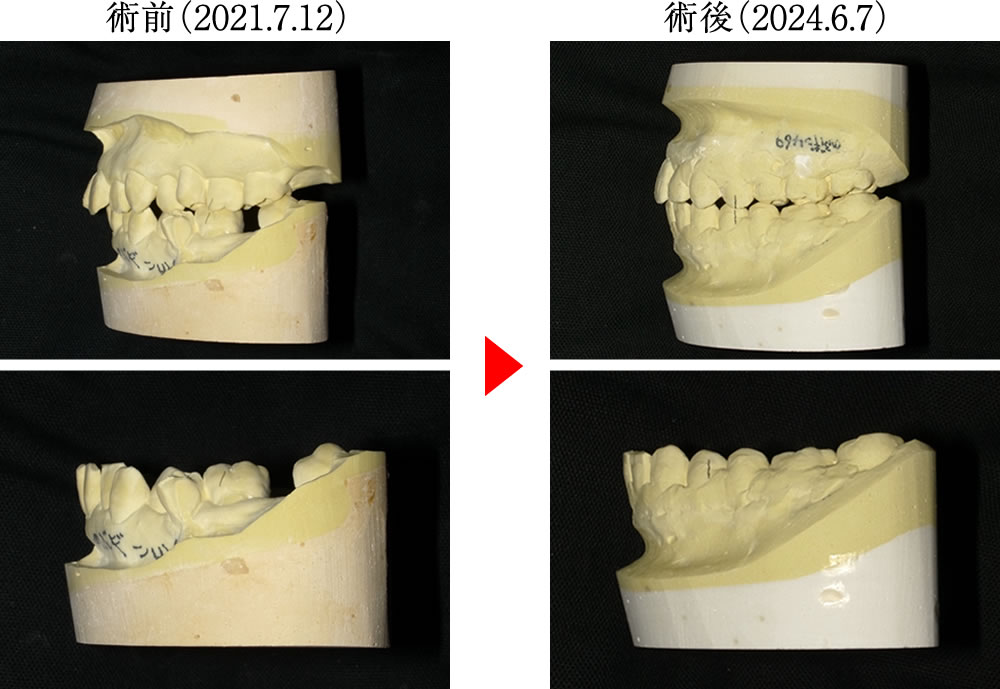

術前は前後的に段差のある二面構造の咬合平面で乱れが見られましたが、術後は咬合平面が理想的なフラットに近づき、バランスの取れた噛み合わせへと改善されました。

また、術前は下顎前歯が後退し、前歯の噛み込みも深い状態でしたが、術後は前歯の位置と角度が理想的に整い、上下の唇のシルエットも美しく改善されました。